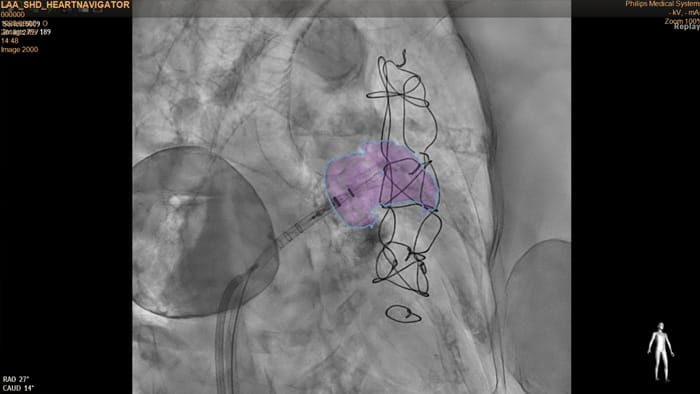

HeartNavigator es una solución de guía de planificación de TAC y superposición en tiempo real que utiliza la segmentación automática para mejorar la facilidad de uso, la velocidad y la reproducibilidad de las intervenciones. En oclusión de la orejuela izquierda, HeartNavigator habilita: